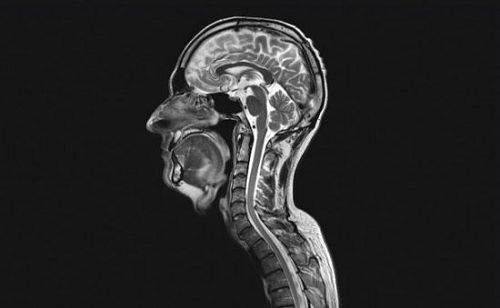

卒中的诊断